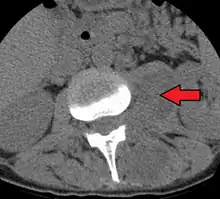

| Paraspinal abscess in the psoas muscle | |

Psoas abscess is a collection of pus in the iliopsoas muscle compartment.[1][2] It can be classified into primary psoas abscess (caused by hematogenous or lymphatic spread of a pathogen) and secondary psoas abscess (resulting from contiguous spread from an adjacent infectious focus).[2]

Psoas abscess may be caused by lumbar tuberculosis. Owing to the proximal attachments of the iliopsoas, such an abscess may drain inferiorly into the upper medial thigh and present as a swelling in the region. The sheath of the muscle arises from the lumbar vertebrae and the intervertebral discs between the vertebrae. The disc is more susceptible to infection, from tuberculosis and Salmonella discitis. The infection can spread into the psoas muscle sheath.[3]